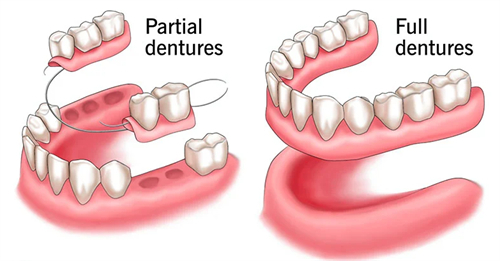

镶活动假牙:5634~17460元起

种植体覆盖义齿:8803~17720元起